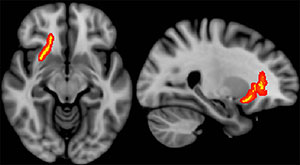

Differences in white matter microstructure may partially account for the variance in functional outcomes among veterans who sustained combat-related mild traumatic brain injury (TBI), according to new research.

Overall, veterans had a mean of 46 health care visits per year during the follow-up period. Cumulative health care visits over time were inversely correlated with diffusion anisotropy of the splenium of the corpus callosum and adjacent parietal white matter. Clinical measures obtained during initial postdeployment evaluation were not predictive of later functional status.

“Our results suggest that diffusion measurements hold the potential to confer important prognostic information in the clinical evaluation of combat-related mild TBI. These findings should encourage continued research efforts to further refine and investigate the clinical utility of diffusion measurements in this setting,” the authors write.